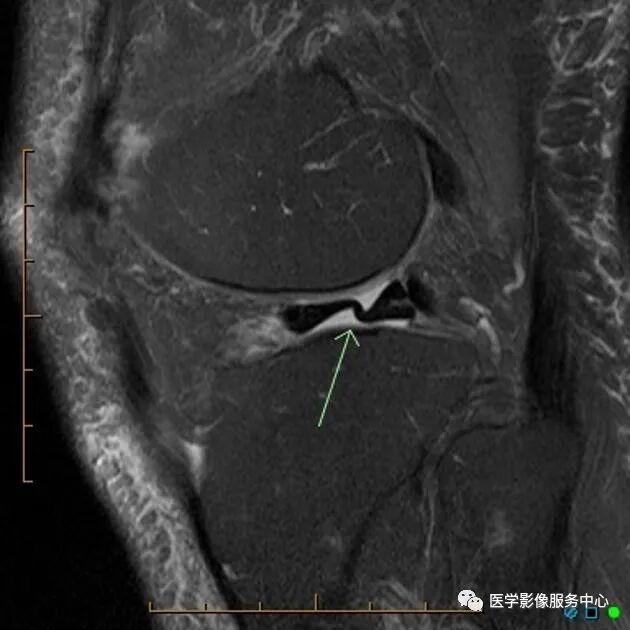

C:矢状位MRI显示腘肌腱(白色箭头),

D:矢状位MRI显示腘肌腱(白色箭头)

外侧半月板后角处的腘肌腱裂孔可被误认为3度半月板撕裂信号。

腘肌腱举例